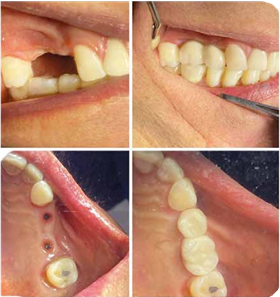

CASO CLÍNICO

Paciente de 35 años acude a nuestra clínica al no tener piezas dentales. Su principal deseo es poder masticar y sentirse mejor al sonreír.

Durante el proceso se optó por la colocación de prótesis fijas sobre IMPLANTES, se puede apreciar los resultados satisfactorios para nuestro paciente.